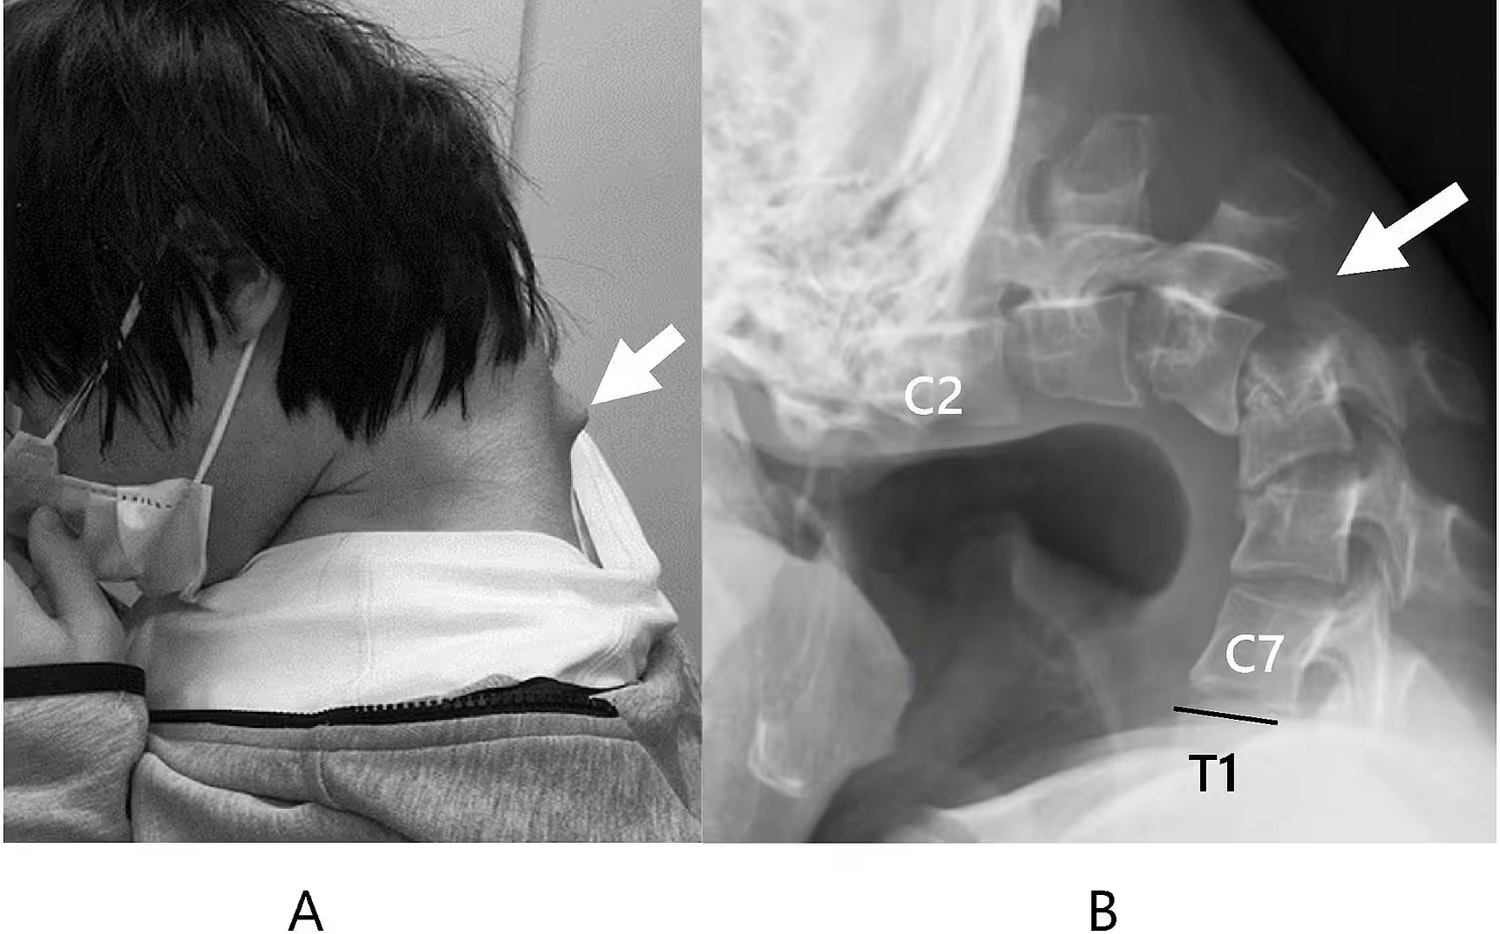

Ein 25-jähriger Japaner entwickelte das Dropped-Head-Syndrom, nachdem er jahrelang in gebeugter Haltung auf sein Handy schaute, wodurch seine Nackenmuskulatur geschwächt und die Halswirbelsäule geschädigt wurde.